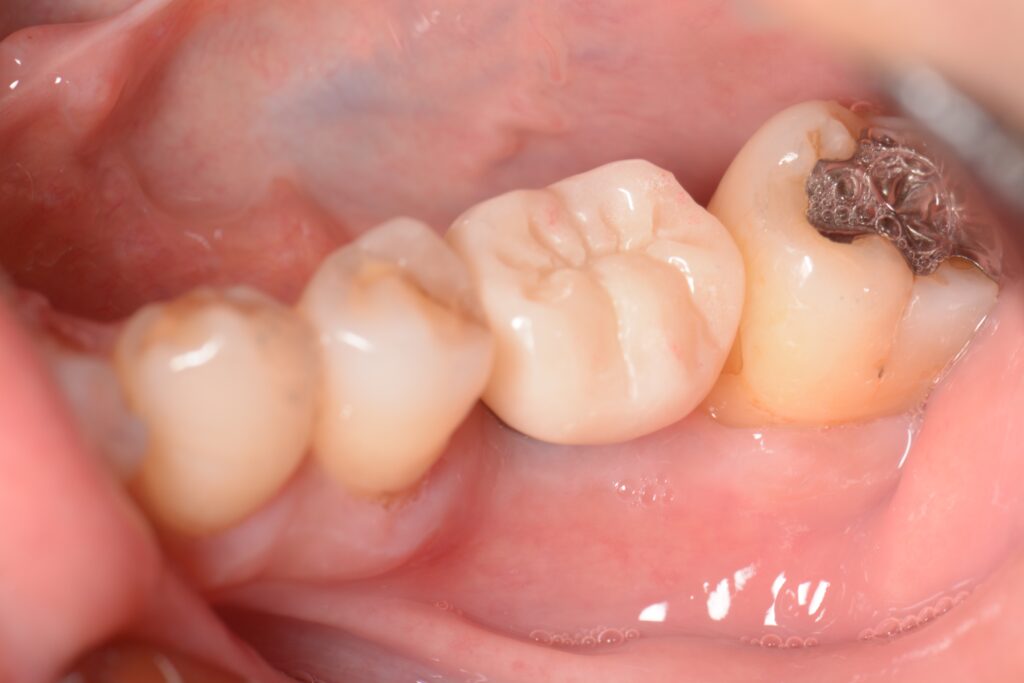

歯がない部分の治療相談で来院された患者様です。 左上奥歯を以前抜歯し、その後義歯を作製したものの違和感があってあまり使用していなかったとのことです。 インプラントも検討したが、骨が少なく難しいと他の歯科医院で言われ義歯を選択したそうです。 レントゲン写真とCTで確認します。 上顎の奥歯の上部には副鼻腔と呼ばれる鼻とつながる空洞が広がっています。 この部分の大きさは元々人によって違うのと、歯を抜いてからの期間が長かったり、歯周病などで状態が悪くなってから抜歯したケースだとこの空洞が広くなり上顎の骨が少なくなっている場合が多くあります。 実際に今回のケースで計測すると上顎には2-3mm程度の骨の厚みしかありません。 インプラントを検討する場合、長さ8mm以上のインプラントで計画を立てることが多いため、骨の厚みが足りない状態です。 短いインプラントを使用するにしても6mmほどの骨の厚みが必要になるため、骨を新たに作らないとインプラントが難しいと考えられます。 この場合、インプラントを諦めて義歯を選択するか、サイナスリフトと呼ばれる外科的に骨を作る処置と併用したインプラントを検討しないといけません。 ”サイナスリフトとは” 上顎の歯を抜いた部分の骨が少ない場合、そのままインプラントをすると上顎洞(副鼻腔)に抜けてしまう可能性があります。 そうならないよう、上顎洞の部分に骨を新たに作り、その部分にインプラントを埋入する方法です。 歯茎を切開、剥離し、骨を露出させます。 骨の部分に一部穴をあけ、上顎洞(副鼻腔)が見えるようにします。 上顎洞内の粘膜を破れないように上に持ち上げます。 粘膜が上に持ち上がったことでできたスペースに人工の骨を填入します。 歯茎を戻します。 骨の厚みが一定量ある場合は、同時にインプラントを入れていきます。 (骨の厚みが極端に少ない場合は、一定期間待機し、人工の骨が自分の骨と同じように置き換わってからインプラントを入れていきます) この状態で6-9ヶ月程度待つとじぶんの骨と同じように置き換わります。 ここまできたら後は被せ物の作製を行なっていきます。 患者様にインプラントを希望される場合、サイナスリフトが必要な旨を説明し、了承を得たため処置に移行しました。 今回は骨の厚みが3mm程度あるため、骨の硬さにも問題がなければサイナスリフトとインプラントを同時に行う方法で計画を立てました。 処置前後で比較します。 インプラントの周りの白い部分が填入した人工の骨です。 インプラントが人工骨に周囲を覆われているのが分かると思います。 処置後は消毒と糸抜きを行い、骨が硬化しインプラントが安定するまで6-8ヶ月程度経過をみていきます。 現在インプラントを扱っている医院は数多くありますが、サイナスリフトなどの骨が少ない時に併用する難易度の高い外科処置に対応していない医院もあります。 アズ歯科桶川院には口腔外科専門医が2名が在籍し、専門性の高い処置を行なっております。 また、インプラント治療が怖い方には麻酔専門医による鎮静下での処置も可能です。 お気軽にご相談ください。 治療期間 9ヶ月 治療費 ¥650,000 + tax インプラント本体+手術料+サイナスリフト 治療のリスク 腫れと痛みが出る可能性がある インプラントが歯周病になる可能性がある